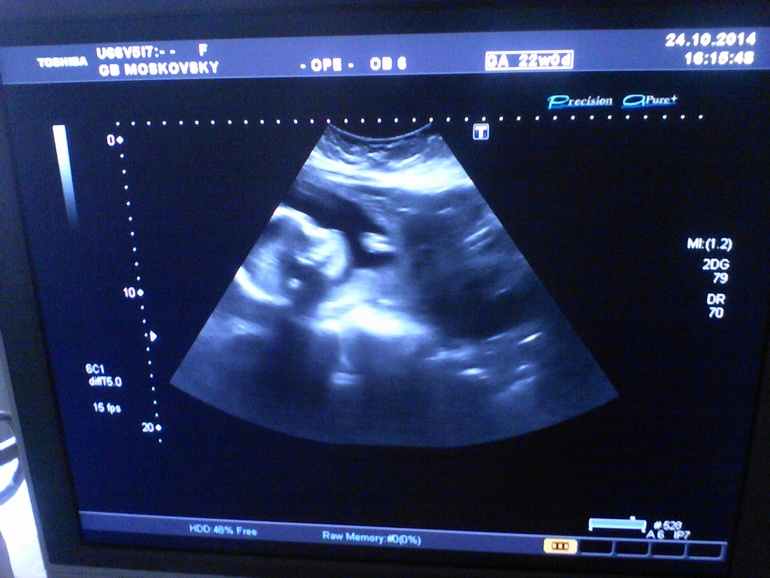

УЗИ, КТГ, доплерСходили МЫ на 2 плановое УЗИ, подтвердили девочку, даже пипку показали))) в этот момент она ковыряла в носу

. Весит 533 гр, рост 35 см. Не длиновата ли для 22 недель?! хотя по УЗИ срок ставят 22 недели 5 дней) все на месте, плацента поднялась, сидим на попе, справа почему-то. То то я думаю, пинает все с одной стороны) Только я вот не поняла, плацента толщиной 24,9мм, II степени зрелости. Это чет не то, да? хотя доктор сказал, все норм. Предположил, что родимся чуть раньше срока, это из-за миомы, но ПДР, как я и считала поставил на 27.02.15. Есть небольшой тонус, опять же из-за узлов, папаверин и магне В6 мне в помощь. Если будет болеть живот, будут ставить капельницы. Ну вот и новости! ттт, не все так страшно) ну и напоследок фотка моей лапочки (сфоткала, как смогла))